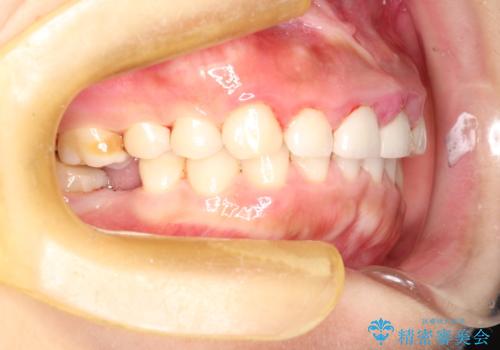

開始前

かなり久しぶりの歯科医院との事で、全体的に古くからの歯垢・歯石が多く付着していたため、自費クリーニング(PMTC)60分コース・歯周ポケット検査(保険適応)を行いました。